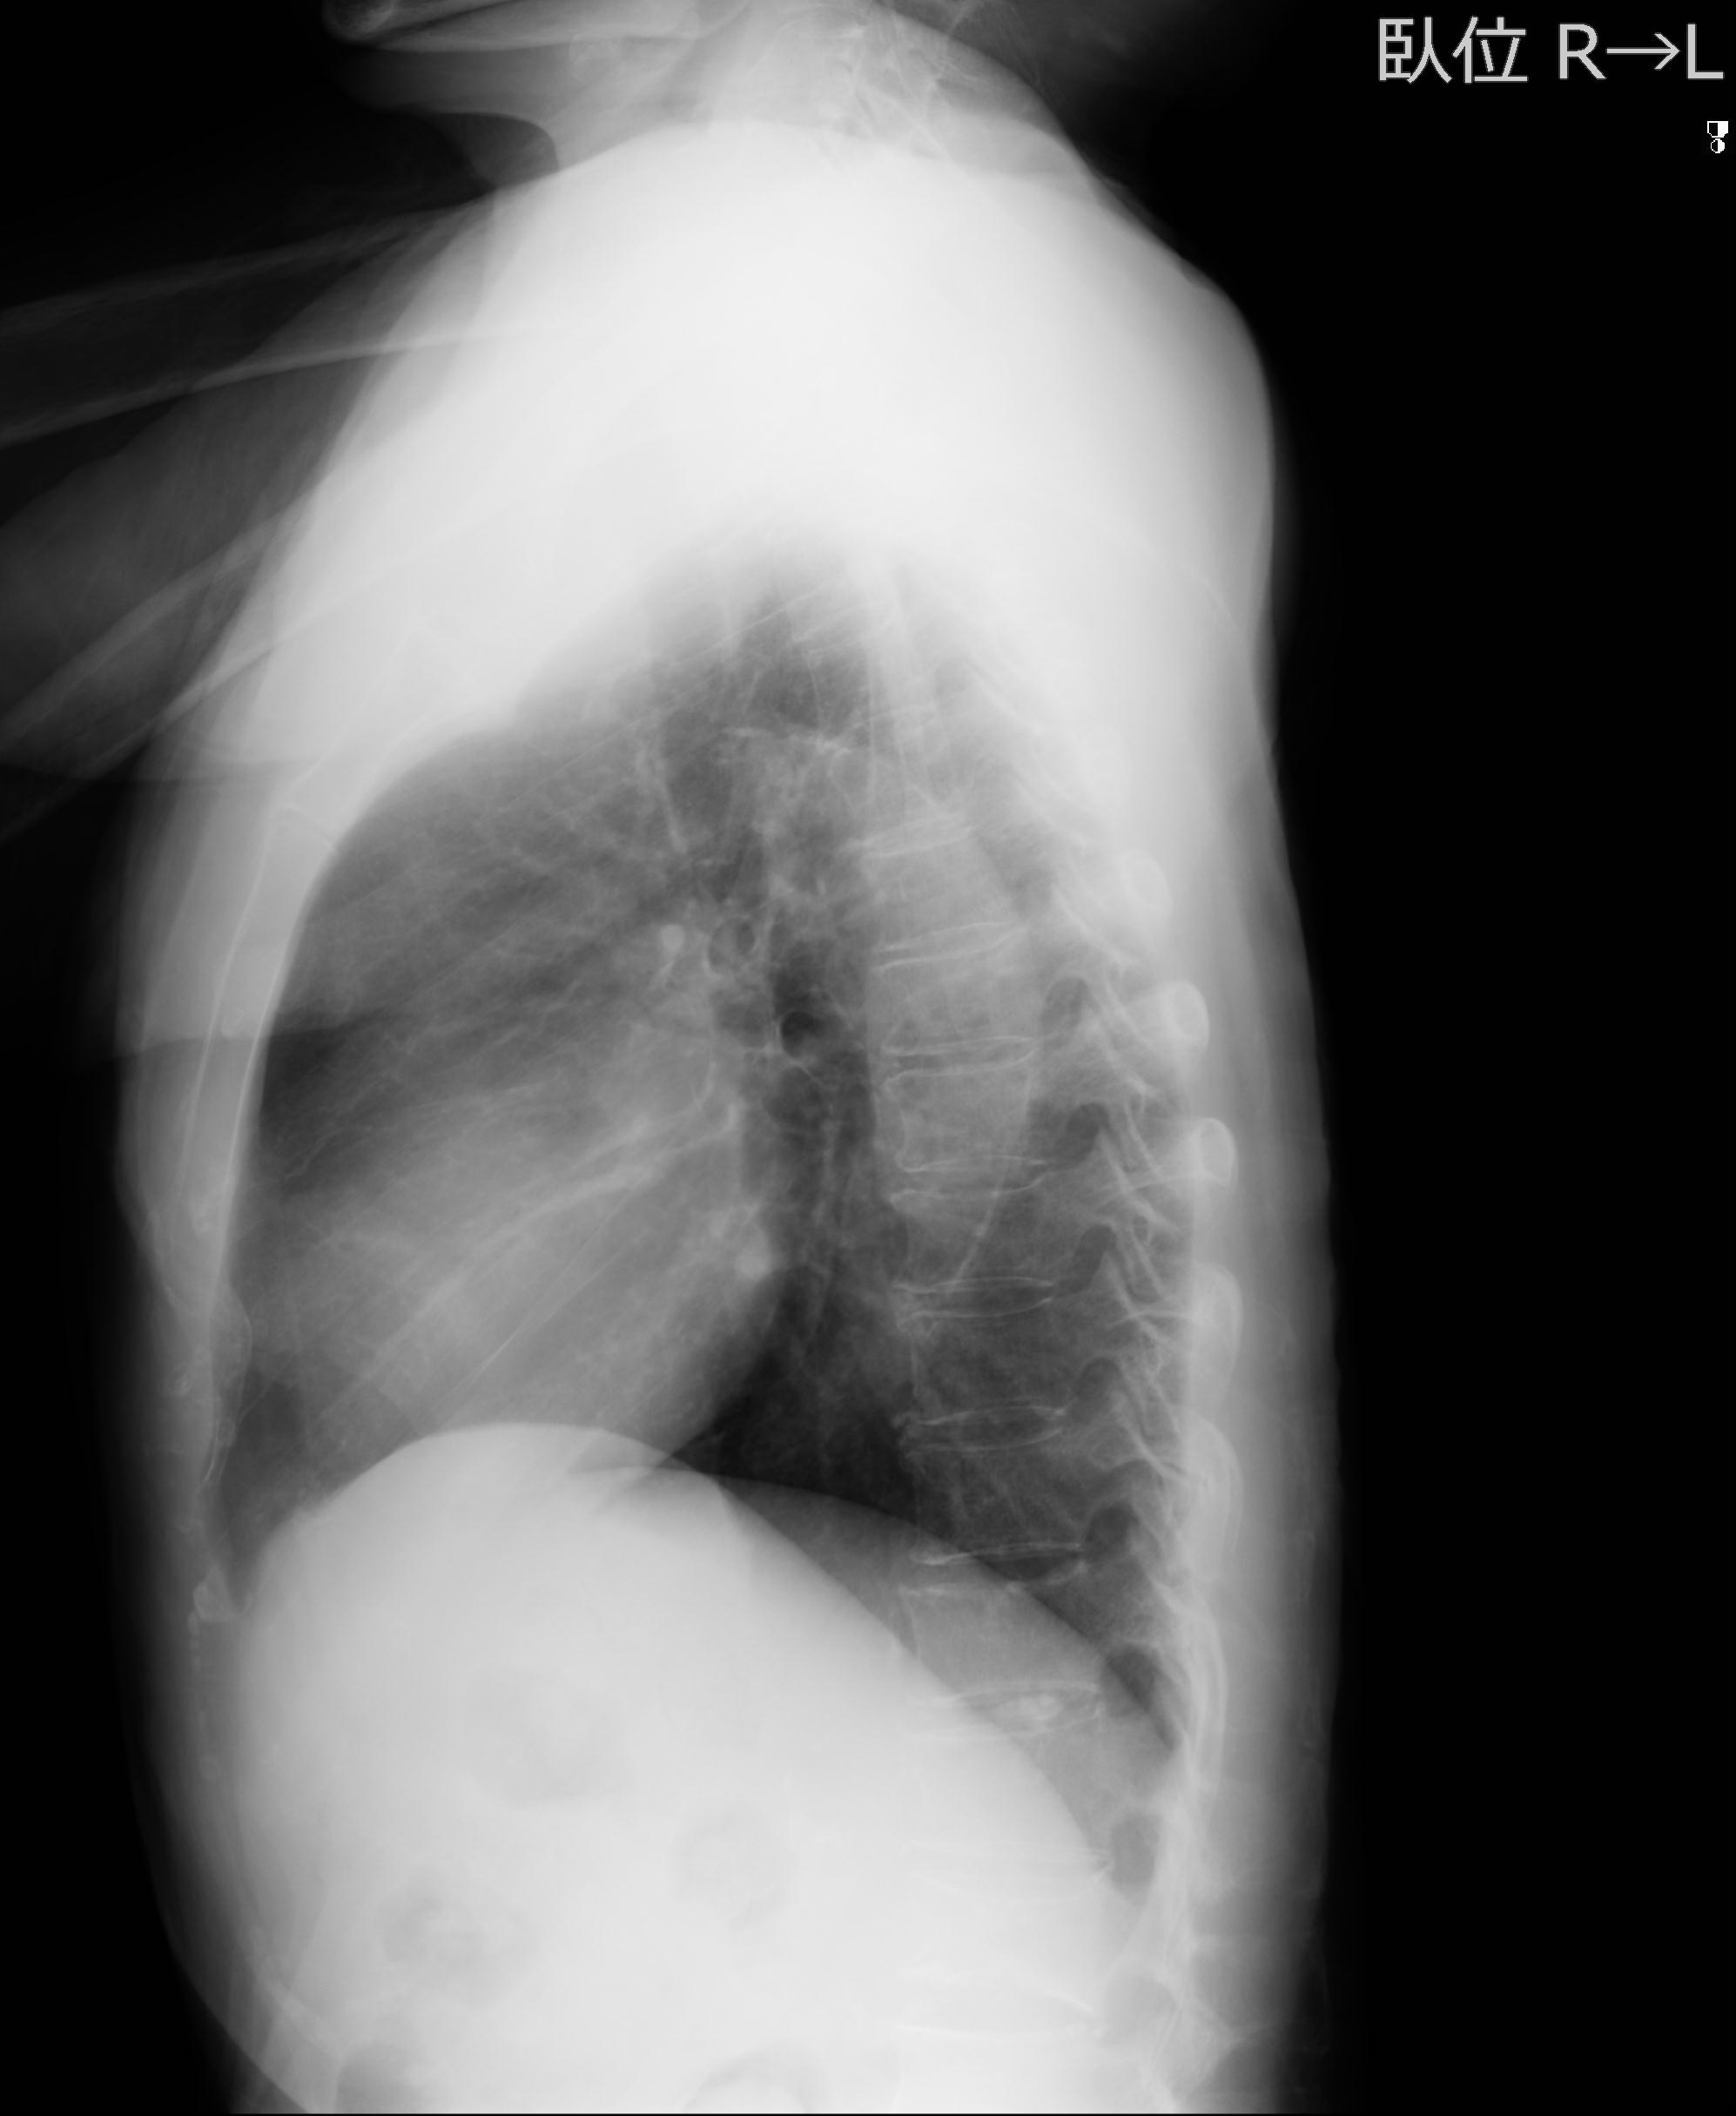

60058 3/9 11/4 右肩 2R+MRI 73歳男性 肩腱板損傷